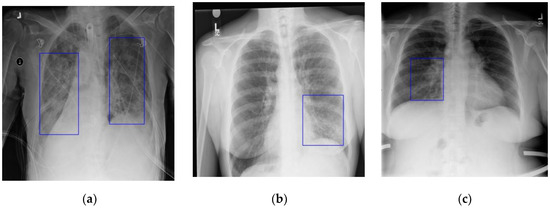

As Table 8 shows, the average precision of PYolo for different IOU thresholds was higher than other algorithms. Faster RCNN is a two-stage algorithm, while SSD, Yolov3 and PYolo are one-stage algorithms. Faster RCNN uses the RPN and it can control the proportion of positive and negative samples well; therefore, the average precision of Faster RCNN was higher than that of SSD and Yolov3. PYolo is an improvement on Yolov3 in feature fusion. Although its mean AP (mAP) was higher than Faster RCNN, PYolo was not able to avoid the imbalance of positive and negative samples. Figure 10 shows the detection effectiveness of the different algorithms. It can be seen that the localization accuracy of PYolo and Yolov3 was higher than that of SSD and Yolov3, and that it had a slight advantage over Faster RCNN. However, for the last image, all four algorithms exhibited false detection and missed detection.

Figure 10.

Detection effectiveness of different algorithms. The blue box in each image is the ground-truth box, and the yellow box is the predicted box: (a) SSD; (b) Faster RCNN; (c) Yolov3; (d) PYolo.